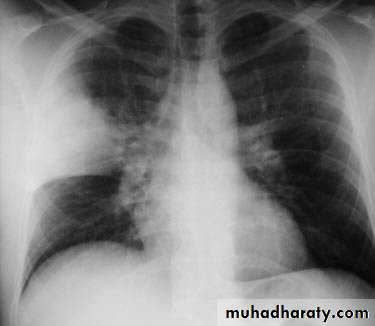

Coexistent debilitating illness and often preceded by influenza. Radiographic features include multilobar shadowing, cavitation, pneumatoceles and abscesses. Dissemination to other organs may cause osteomyelitis, endocarditis or brain abscesses. Mortality up to 30%.

Chest X-ray show multiple lung abscessStaphylococcus pneumonia

Klebsiella pneumoniae; a gram-negative baclli3- Klebsiella pneumonia; More common in aged men, malnutrition and alcoholics. Upper lobe involvement typical. Low platelet count and leucopenia.